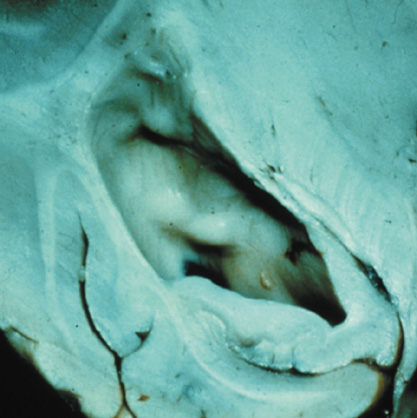

1. Superficial cortical sclerosis (parenchymal hamartoma) which distort the gyri. Microscopy shows large atypical fibrillary type astrocytes with few associated neurons and areas of calcification.133 The numerous abnormal glial processes and fibers make the tissue abnormally firm or “sclerotic” on palpation (Fig. 13).132

Fig. 13. Tuberous Sclerosis Complex: “cortical sclerosis.” Numerous abnormal glial processes make the tissue abnormally firm or “sclerotic” on palpation.132